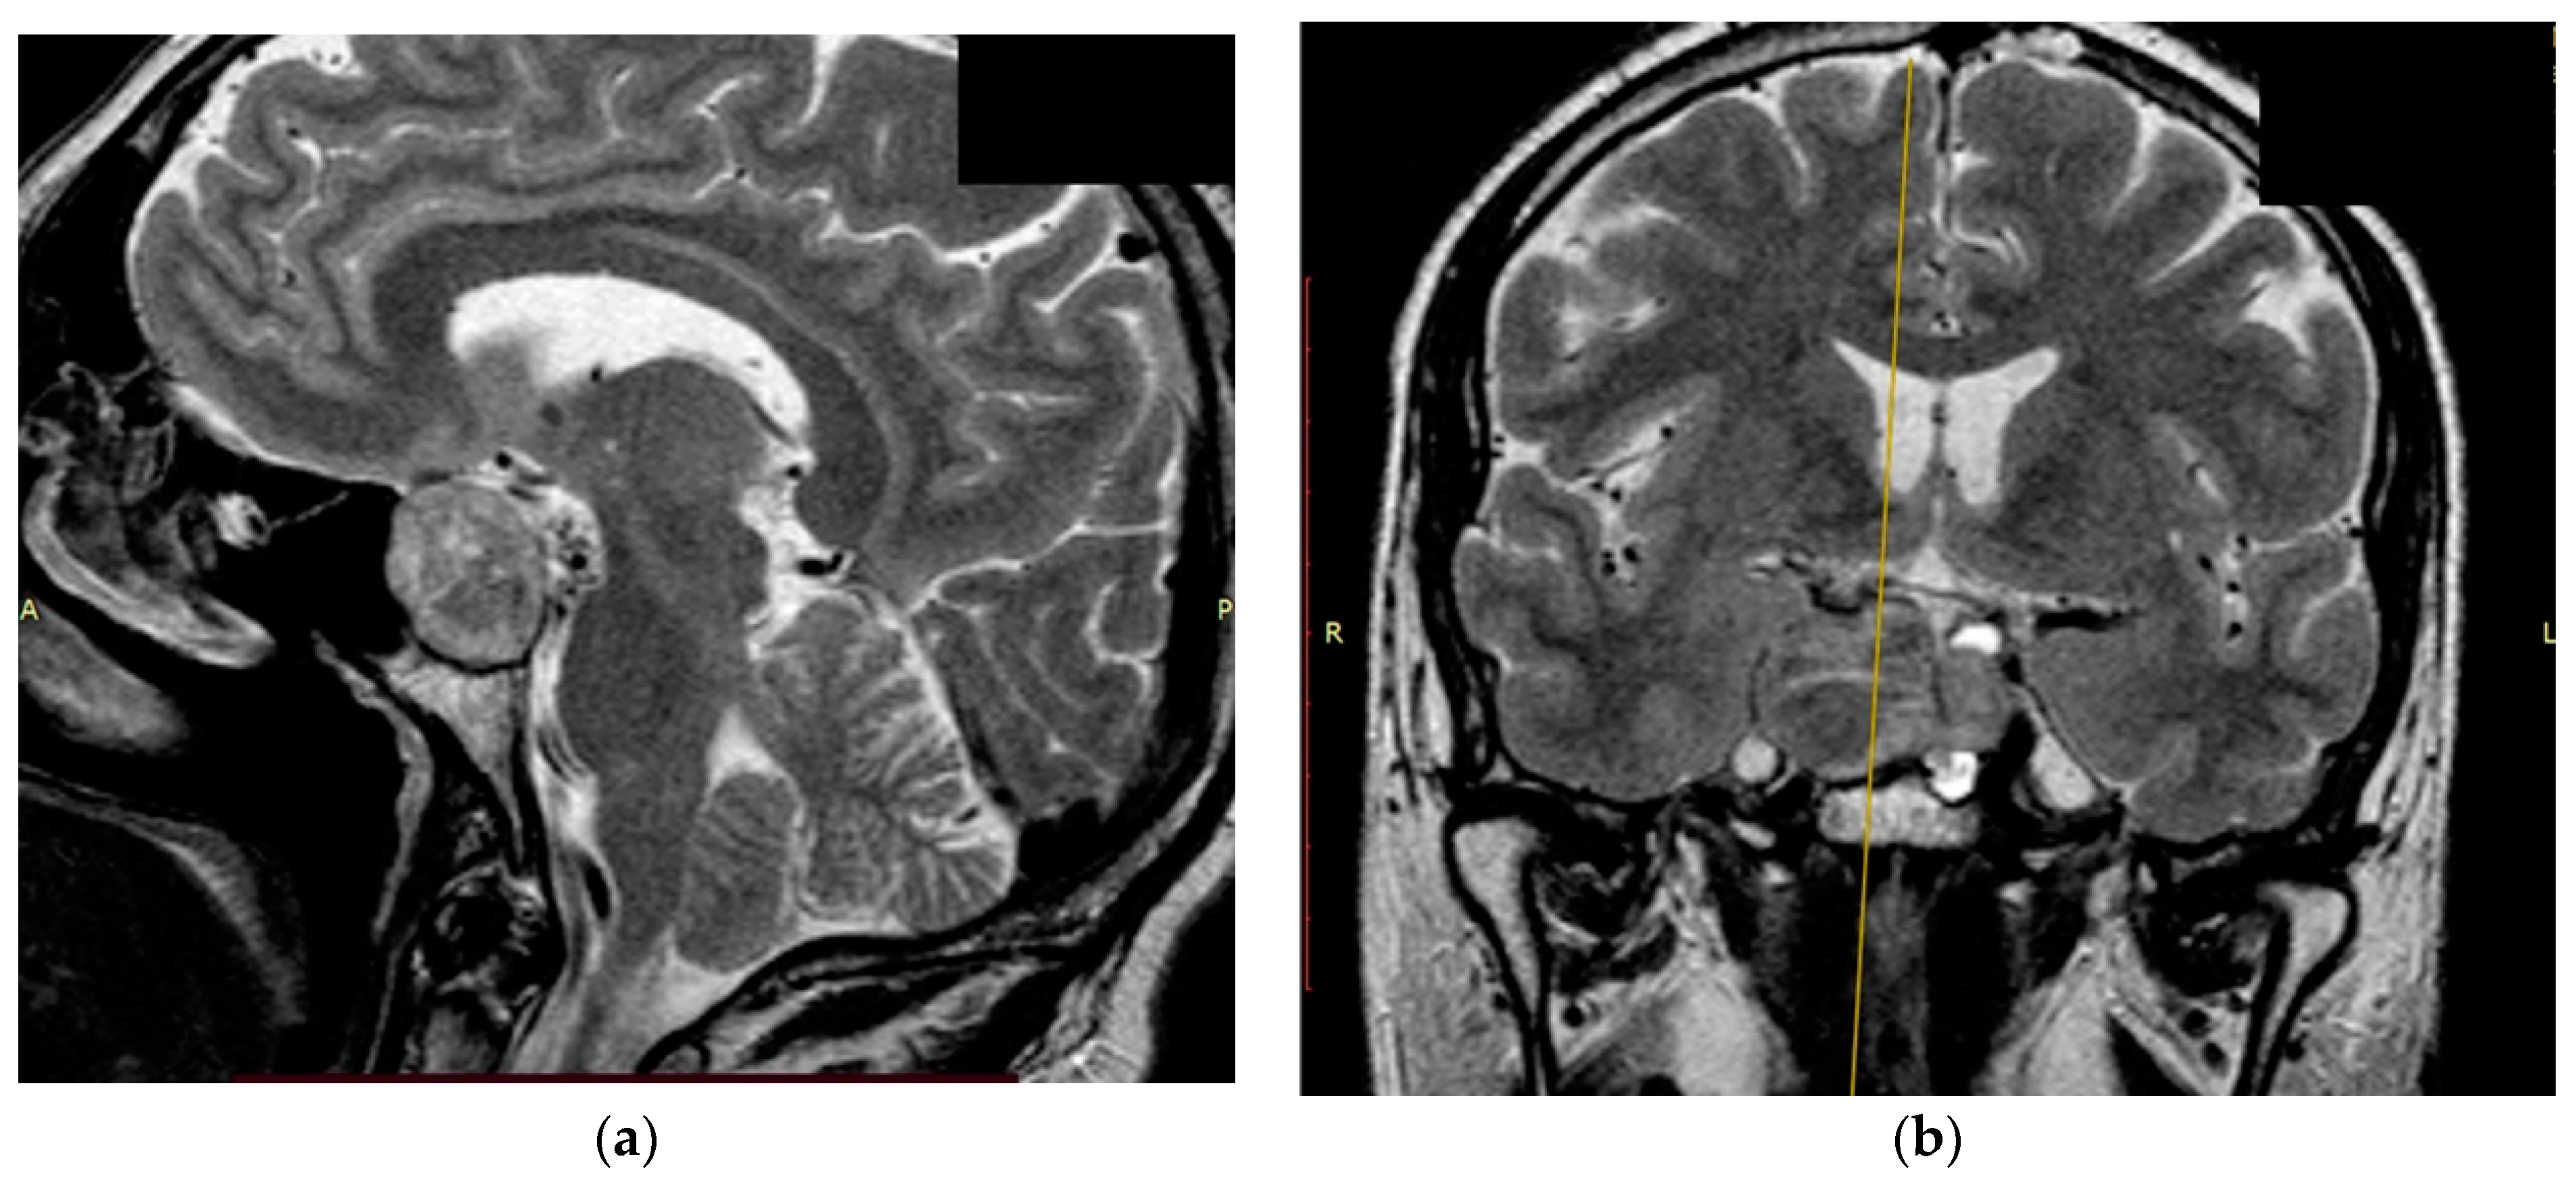

2.3. Clinical Part

The study’s clinical part involved 3 patients. Patients 1 and 2 were diagnosed with hormonally inactive pituitary macroadenomas, and patient 3 with a hormonally active one. All patients underwent endoscopic transnasal removal of the tumor at A.I. Evdokimov Moscow State University of Medicine and Dentistry. Two patients (1, 2) included in the study had previously undergone surgery with resection of the tumor at different times and had continued tumor growth. After the initial intervention, according to the histological examination, patients were diagnosed with PA, while Patient 3 had a primary PA. Additionally, at the preoperative stage, the infiltrative nature of tumor growth into the surrounding tissues was assumed. All patients were admitted to the clinic in satisfactory condition, without focal neurological symptoms. Patients 1 and 2 of the concomitant diseases had hypertension, and Patient 3 had secondary hypothyroidism. Patients 1 and 2, both in the preoperative period and after the surgery, took hormone replacement therapy for hypopituitarism: hydrocortisone and desmopressin. Patient 3 was taking L-thyroxine for a concomitant disease. None of the patients, either in the preoperative period or after the surgery, took chemotherapy drugs, since at the moment they are not included in the standard of treatment for patients with pituitary adenomas, given the benign nature of these types of tumors. All patients underwent a study of the hormonal profile and MRI of the brain with contrast enhancement with an assessment of the tumor spread and its interaction with the main nerve structures (Figure 3, Figure 4 and Figure 5). The patients’ primary characteristics are presented in Table 1.

Figure 4. Preoperative T1 MRI images of Patient 2 with contrast enhancement: (a) axial projection, endosuppralaterosellar mass with extension to the right cavernous sinus, and (b) frontal projection, endosuppralaterosellar mass, with compression of the chiasm, spread to the right cavernous sinus with ingrowth of the right internal carotid artery.